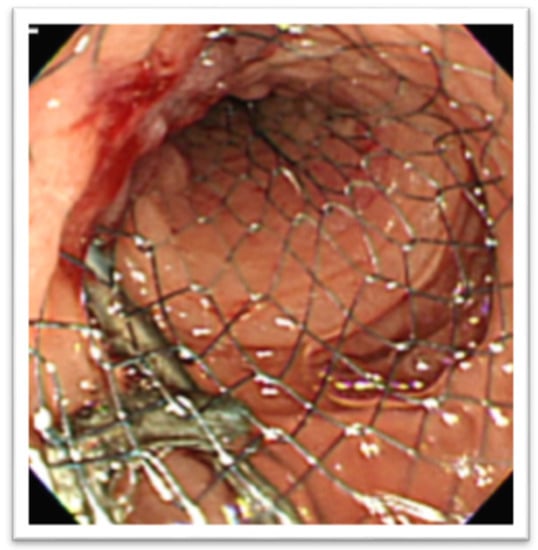

In the setting of malignant GOO, several randomized trials have compared the outcomes of surgical gastrojejunostomy (SGJ), endoscopic SEMS placement (Figure 11), and EUS-GEA anastomosis (Figure 12) [2,13,14,15,16,17]. The main limitation of SGJ is commonly considered its invasiveness, associated with the occurrence of post-surgical adverse events, as with gastroparesis and post-operative infections [2,13].

Figure 11. Duodenal self-expandable metal stent (SEMS).